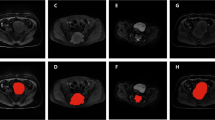

A 25-year-old male patient who visited the ED complaining of abdominal pain. CT images show fluid distension of small bowel loops with transition at the terminal ileum (arrowhead). The contrast among the bowel wall, visceral fat, and intraluminal fluid is more evident in DL-SCE-CT than in NECT. The patient was admitted for management of Crohn’s disease flares. In this case, all of reviewers made the correct diagnosis (small bowel obstruction at terminal ileum) regardless of DL-SCE-CT. However, two more radiologists made correct disposition decision (admission for medical management) after review of DL-SCE-CT. Moreover, with the aid of DL-SCE-CT, the confidence of the diagnosis and disposition decision increased from 4.17 to 4.50 and 4.00 to 4.50, respectively.

A 65-year-old female patient who visited the ED complaining of abdominal pain and fever. CT images show intrahepatic duct stones (arrowhead) with dilated upstream bile ducts. The contrast among the liver parenchyma, fluid within the dilated bile duct, and stones within the bile duct are more evident in DL-SCE-CT than in NECT. The patient was admitted for management of obstructive cholangiohepatitis. In this case, 100.0% (6/6) and 83.3% (5/6) of radiologists made the correct diagnoses and disposition decisions (intrahepatic duct stones with biliary obstruction, admission for medical management), regardless of DL-SCE-CT. However, both radiologists’ confidence in the diagnosis and disposition decisions improved from 3.83 to 4.00 and 4.17 to 4.50, respectively, with the aid of DL-SCE-CT.